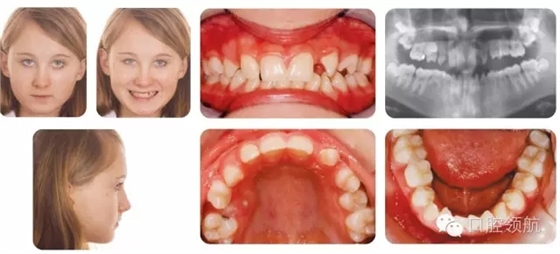

12歲的女性患者,為II類2分類錯(cuò)牙合,中度骨性II類,后縮側(cè)貌,下頜發(fā)育不足(圖2.23)。

圖2.23

X線片檢查顯示UL3和LR5先天缺失,LRE滯留,預(yù)后較好。

● Ⅱ類切牙關(guān)系。

● UR5和下切牙擁擠。

● 上頜第一前磨牙扭轉(zhuǎn)。

● 上頜后牙段間隙。

● UL3和LR5先天缺失。

● LRE滯留(預(yù)后較好)。